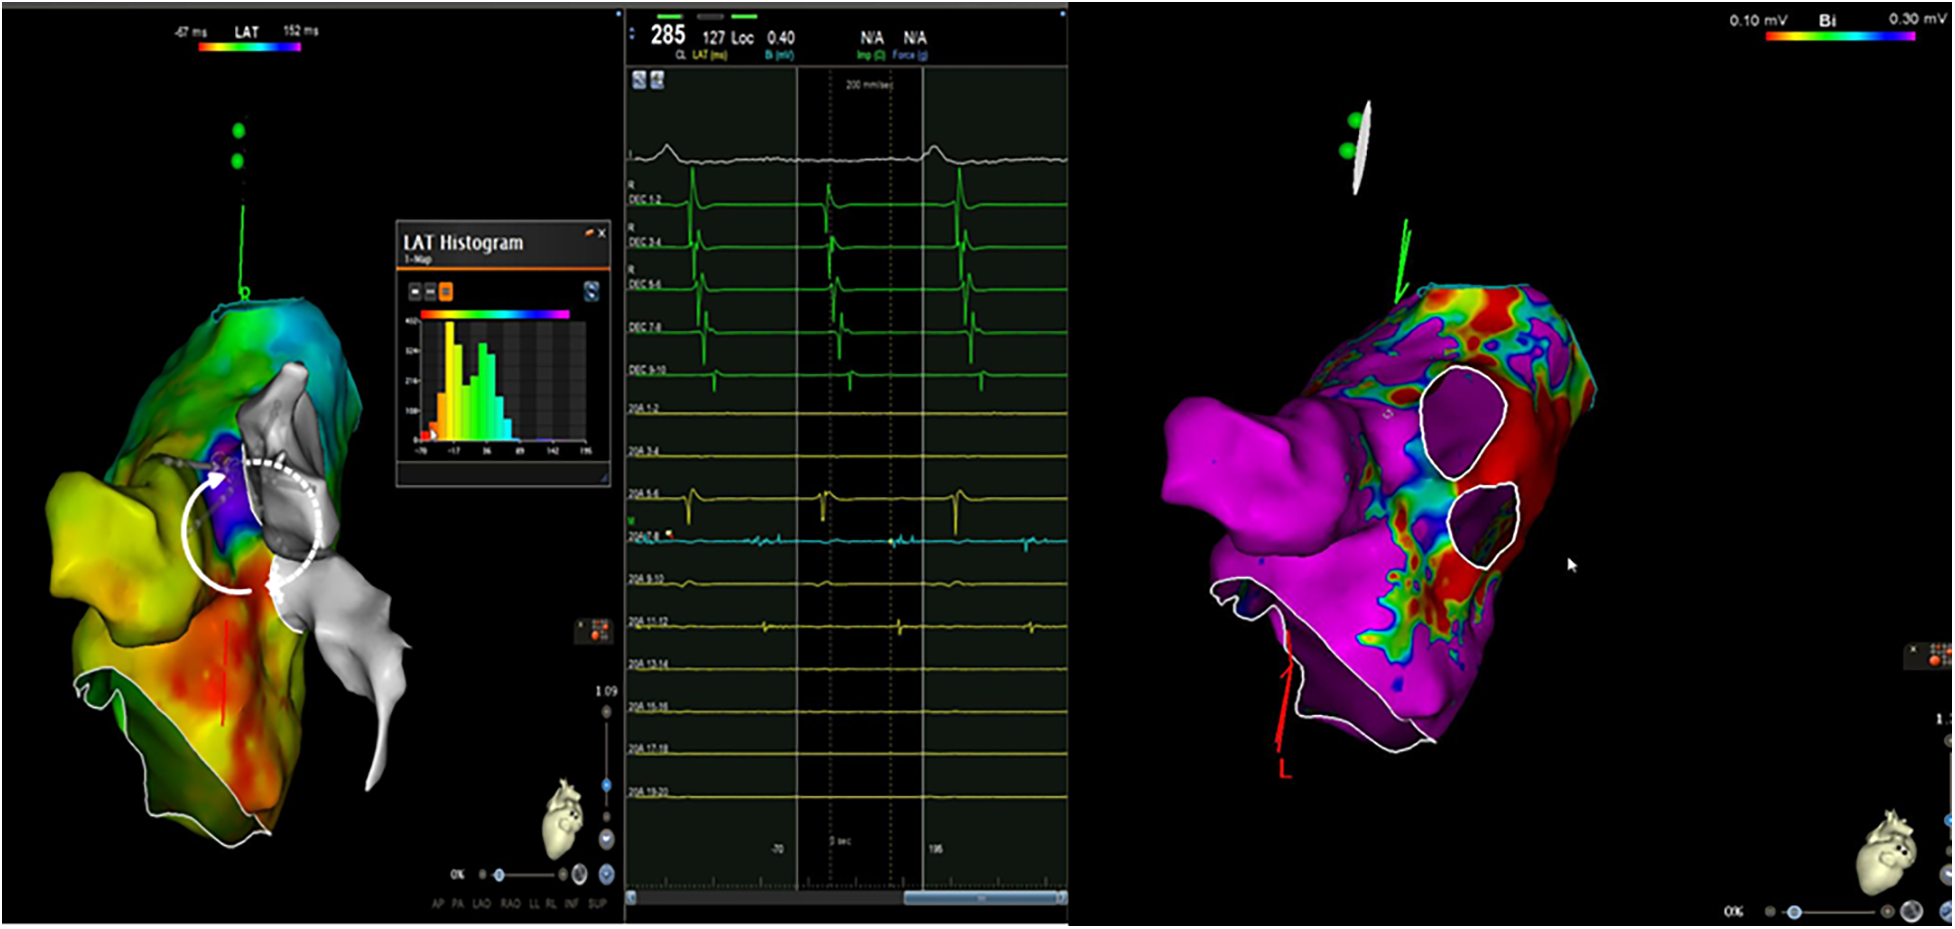

An electrocardiogram (ECG) was quickly performed and an atrial tachycardia was observed (Figure 1). All blood test results were in normal range and there was no sign of infection. Then, echocardiography was performed and the left ventricle's ejection fraction was measured at 52% with normal cardiac structures. Next, an electrophysiological study (EPS) was conducted. The tachycardia cycle length (TCL) of the AT was found to be 285 ms, and CS activation was eccentric and compatible with left atrial origin. The LA was electroanatomically mapped using a CARTO 3D mapping system (Biosense Webster, Diamond Bar, CA, USA) with a high-density mapping catheter (Pentaray). The local activation time (LAT) map demonstrated that all pulmonary veins and the posterior wall were already isolated. A local reentry was detected between the LSPV and the LAA, and wavefront collision was seen on the anterior wall consequent to activation mapping, and therefore, no perimitral AT was suspected. This could have been easily excluded by performing consecutive entraining maneuvers at the CS proximal and distal regions, and these should be done when the mechanism of tachycardia cannot be understood. However, these maneuvers were not performed in this patient because of the fear of unwanted termination of the tachycardia and because the activation map clearly showed no perimitral AT. This area also harbored low-amplitude fragmented diastolic electrograms (EGMs) compatible with the critical region. However, 17% of the tachycardia circuit was found to be missing in the LAT histogram, suggesting another yet-unmapped site, i.e., the epicardial surface (Figure 2). Given the typical proximity of the Marshall bundle to this area, an element of suspicion arose regarding the direct participation of the MB in the tachycardia circuit.

Figure 2

An electroanatomic mapping of the left atria and histogram of the LAT mapping during a tachycardia event and a bipolar map of the left atrium before ethanol ablation of the VOM (the propagation of the local reentry of the tachycardia is shown in the form of white arrows. The white arrows with dots show epicardial activation through the Marshall bundle).